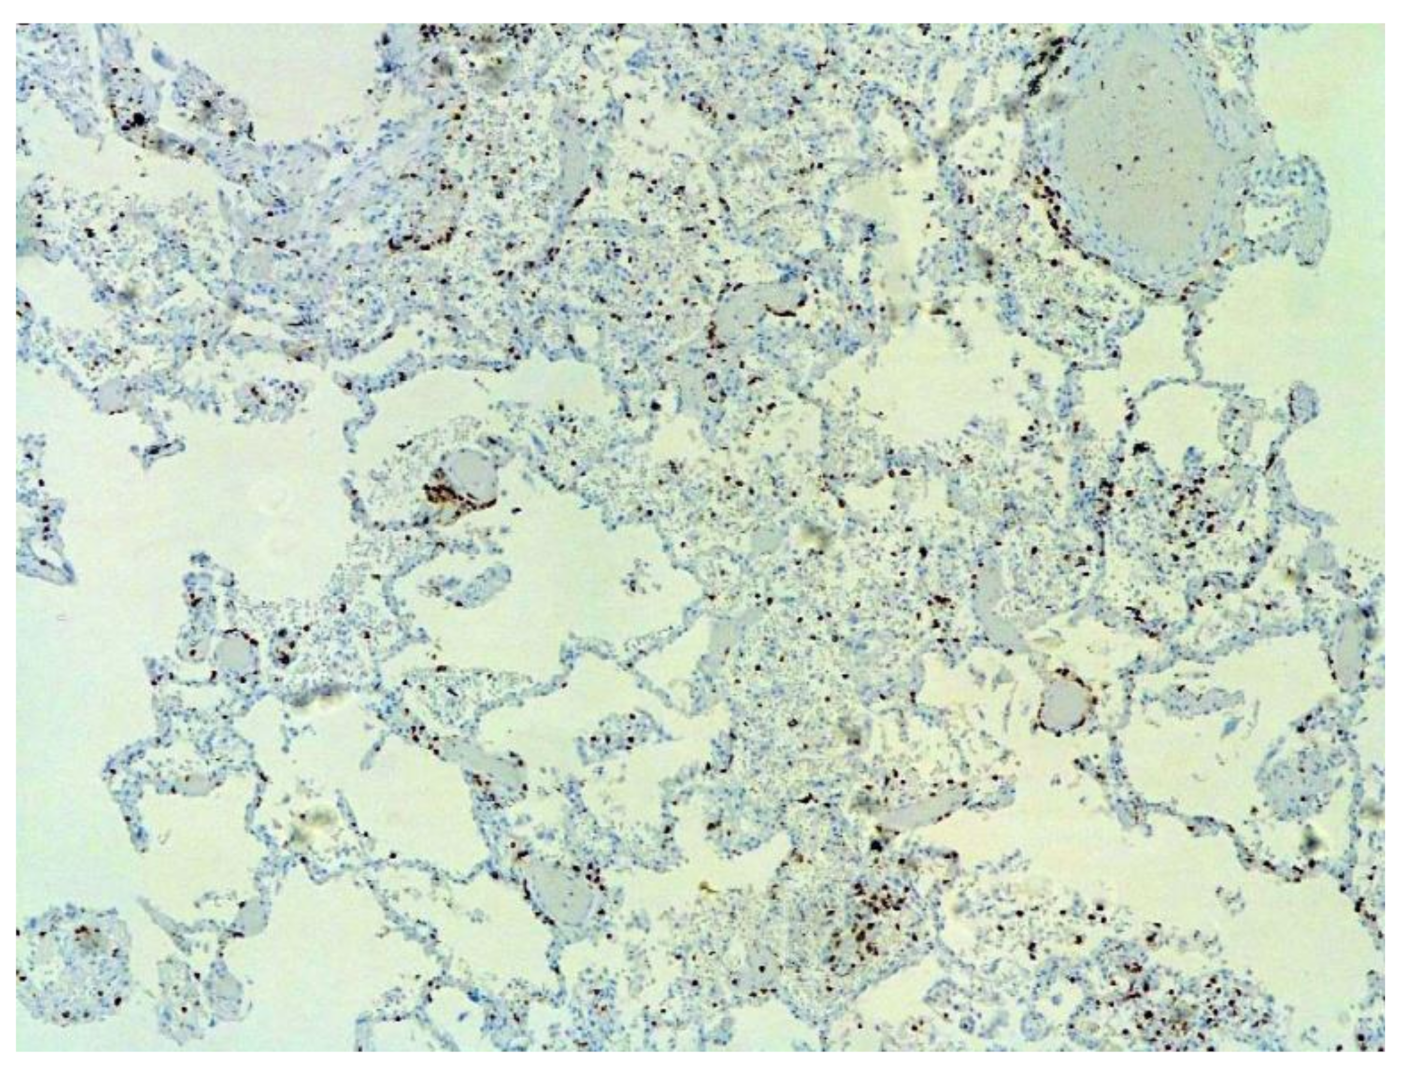

The dynamics of changes in ARDS associated with COVID-19 can only be judged by analogy with SARS and influenza A/H1N1pdm. In the late (productive) stage (after 7–8 days or more from the onset of the disease) of diffuse alveolar damage, macroscopically the lungs are enlarged, low-air, dense, fleshy, and can resemble the density of the liver, sometimes with diffuse whitish layers and areas of different sizes. Microscopically, siderophages, a relatively (in comparison with swine influenza) small number of hyaline membranes (Figure 9), fibrin, squamous metaplasia of the bronchial, and bronchiolar and alveolar epithelium can be detected in the lumens of the alveoli, respiratory and terminal bronchioles, the thickening of the interalveolar septa due to sclerosis, lymphoid (mostly CD3+ and CD 8+) (Figure 10 and Figure 11) and macrophage (Figure 12) infiltration, and the proliferation of type II alveolocytes. The nature of cytoproliferative changes of the epithelium in the trachea and bronchi remains unclear. In the final stage of the disease, sections of fibrous tissue may develop in all parts of the lungs (usually in the lower lobes) (Figure 13), which contributes to the development of chronic respiratory failure. It is notable that near the overgrowth of collagen fibers in the lungs, neoangiogenesis is also typical (Figure 14). The electron microscopic study revealed changed viral particles (Figure 15).

Figure 10. Numerous CD3+ lymphocytes in lung. IHC ×50.